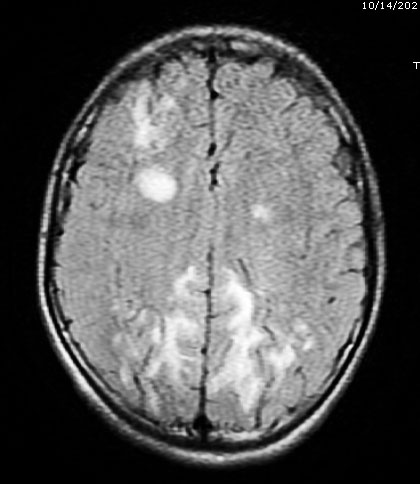

Bệnh nhi Bàn T N (sinh năm 2008, trú tại TP Hạ Long, Quảng Ninh) cấp cứu tại Bệnh viện Bãi Cháy trong tình trạng suy hô hấp, sốt cao, phù toàn thân, tăng huyết áp. Một tuần trước nhập viện trẻ xuất hiện mụn nước cẳng chân, vùng đầu, kèm to nặng hai chân, sau đó trẻ sốt, ho húng hắng, đau đầu, co giật toàn thân bốn cơn, li bì. Ngay khi tiếp nhận bệnh nhi, các bác sĩ đã thăm khám lâm sàng và chỉ định các xét nghiệm cận lâm sàng. Kết quả xét nghiệm máu cho thấy các chỉ số nhiễm khuẩn tăng cao, hình ảnh chụp CT phổi có tổn thương đông đặc lan tỏa hai bên, hình ảnh chụp MRI sọ não có tổn thương viêm, siêu âm có tràn dịch đa màng.

Hình ảnh chụp MRI sọ não có tổn thương viêm